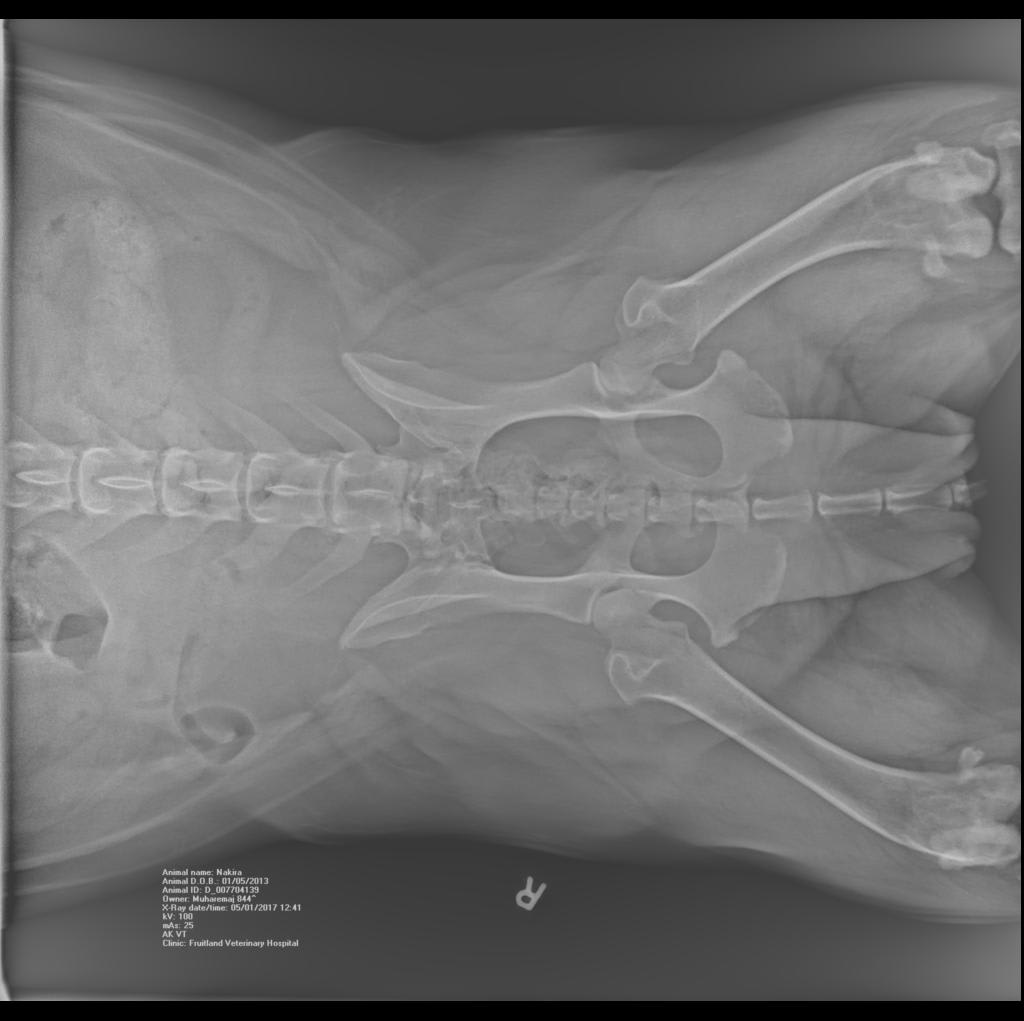

Hello there, I am looking for an expert HONEST opinion about my dog's knee condition...she is only 4 years old, and can barely walk (hind legs). A mastiff-bulldog mix, cca 130 lbs, ( on a special vet diet) spayed female. Motility problems started cca 18 months ago. I am attaching 3 x-rays. Is this a progressive illness and what is your recommendation (no surgeries). Thank you.